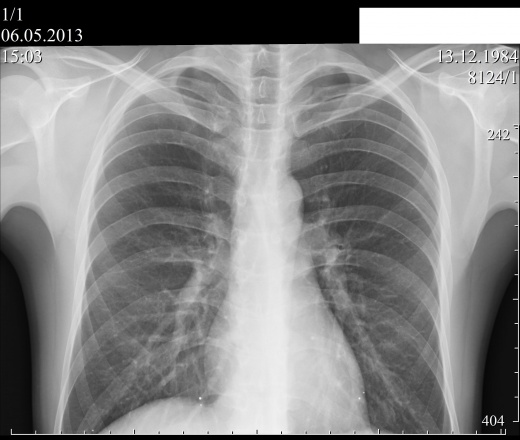

Пациент 28 лет.По поводу травмы рёбер назначена R-графия грудной клетки. Признаков травматических повреждений не нашли, но нашли другое. Работает на деревообрабатывющем стаке, проходил срочную службу. Жалоб связанных с ниходкой не предъявляет.На коже следов проникновения инородных тел нет. Чем могут быть обусловлены находки?

На скопии смотрел, да это в лёгких ( только вопрос, как металл туда проник, если на коже нет следов проникновения). Это точно не металлическая стружка, так по форме инородные тела строго шаровидной формы).

"Он случайно не охотник." Вы намекаете на дробь- это точно не дробь и дробь при таком массовом поражении что-то оставила бы на коже.

Инъекции металлической ртути у любителей "поторчать", когда ширева другого нет, выглядят несколько иначе.

Мы с коллгами на работе думаем, что это всего скорее ртуть. Но, путь проникновения в организм, вероятно иной. Может быть случайно когда-то вдохул ртуть , например когда разил градусник-ртуть попала в трахео-бронхиальное дерево и и спуситалась в бронхи нижних отделов лёгких. Я спрашивал об этом пациента, но он говорит, что такого не помнит. Но, это только версия...